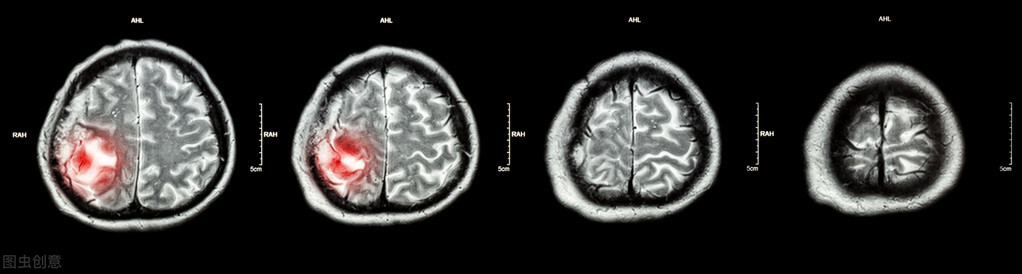

恶性: 恶性脑肿瘤含有癌细胞,通常没有清晰的边界。它们被认为具有生命危险,因为它们迅速生长并侵入周围的脑组织。

原发性: 起源于脑细胞的肿瘤称为原发性脑瘤。原发性脑部肿瘤可能扩散到大脑其他部位或脊椎,但很少扩散到其他器官。

转移性: 转移性或继发性脑瘤始于身体的另一部分,然后扩散到大脑。这些肿瘤比原发性脑瘤更为常见,并以它们开始的位置命名。